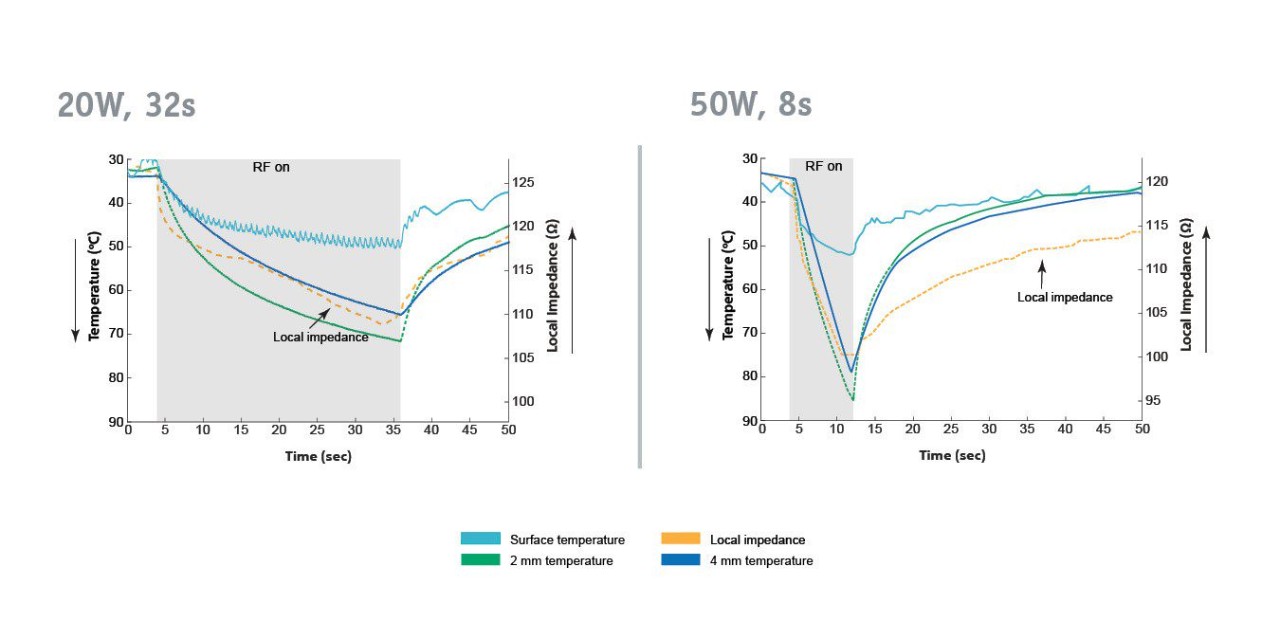

Pre-Clinical Data

Intra-lesion Temperature Rise And Local Impedance Drop Predictive of Lesion Growth on RF Ablation Catheter With Mini Electrodes (Download Poster)

Abstract Accepted to Heart Rhythm Annual Meeting, Garrott, et al., May 2020. Distributed with permission from the Heart Rhythm Society.